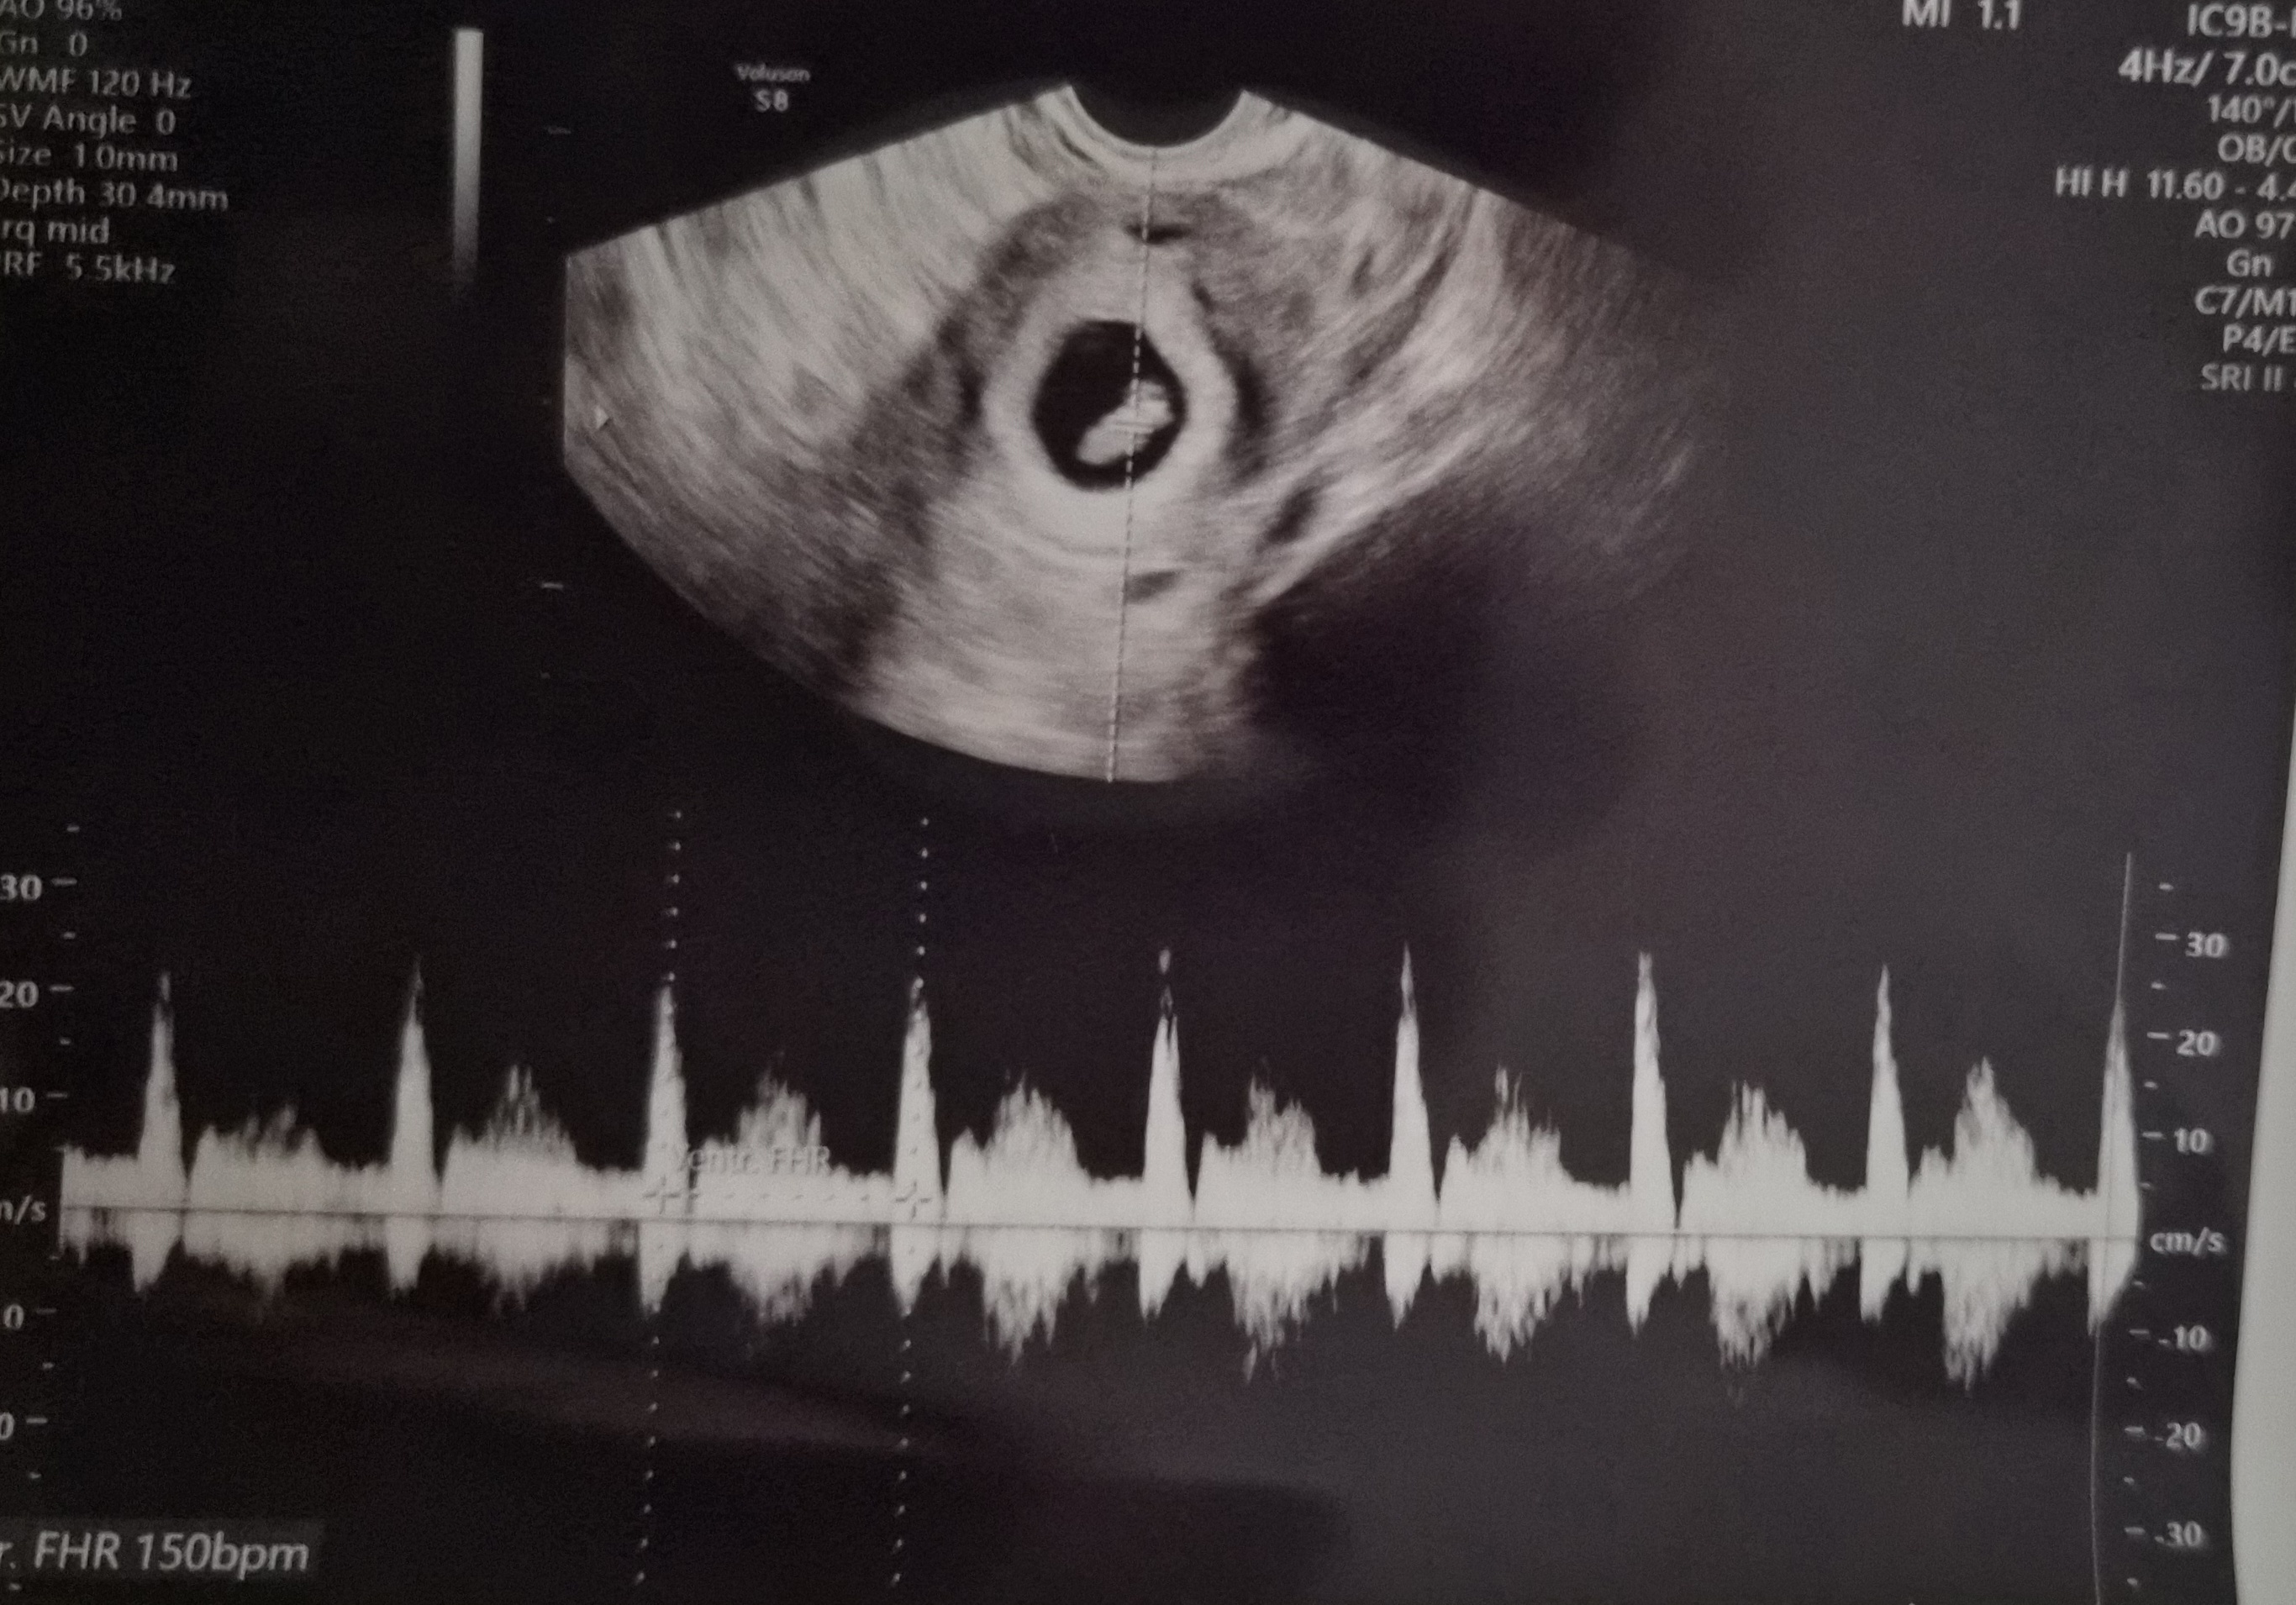

| 치료 도중 느꼈던 가장 기뻤던 순간과 절망적인 것들은 무엇인가요? 잊지 못할 경험이 있나요? | 가장 기뻤던 순간은 이식 후 처음으로 아기집을 확인하고, 이어서 건강한 심장소리를 들었을 때예요. |